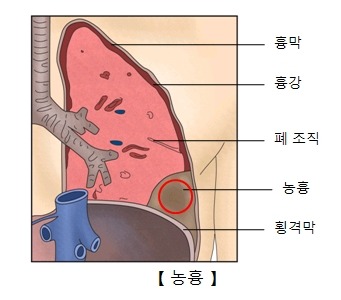

폐렴이 진행되면 패혈증이나 쇼크가 발생할 수 있습니다. 국소적인 합병증으로 흉수, 농흉, 폐농양 등이 생길 수 있습니다. 모든 폐렴 환자에게 합병증이 동반되는 것은 아닙니다. 하지만 고위험군 환자는 합병증이 생길 확률이 높으므로 주의가 필요합니다.